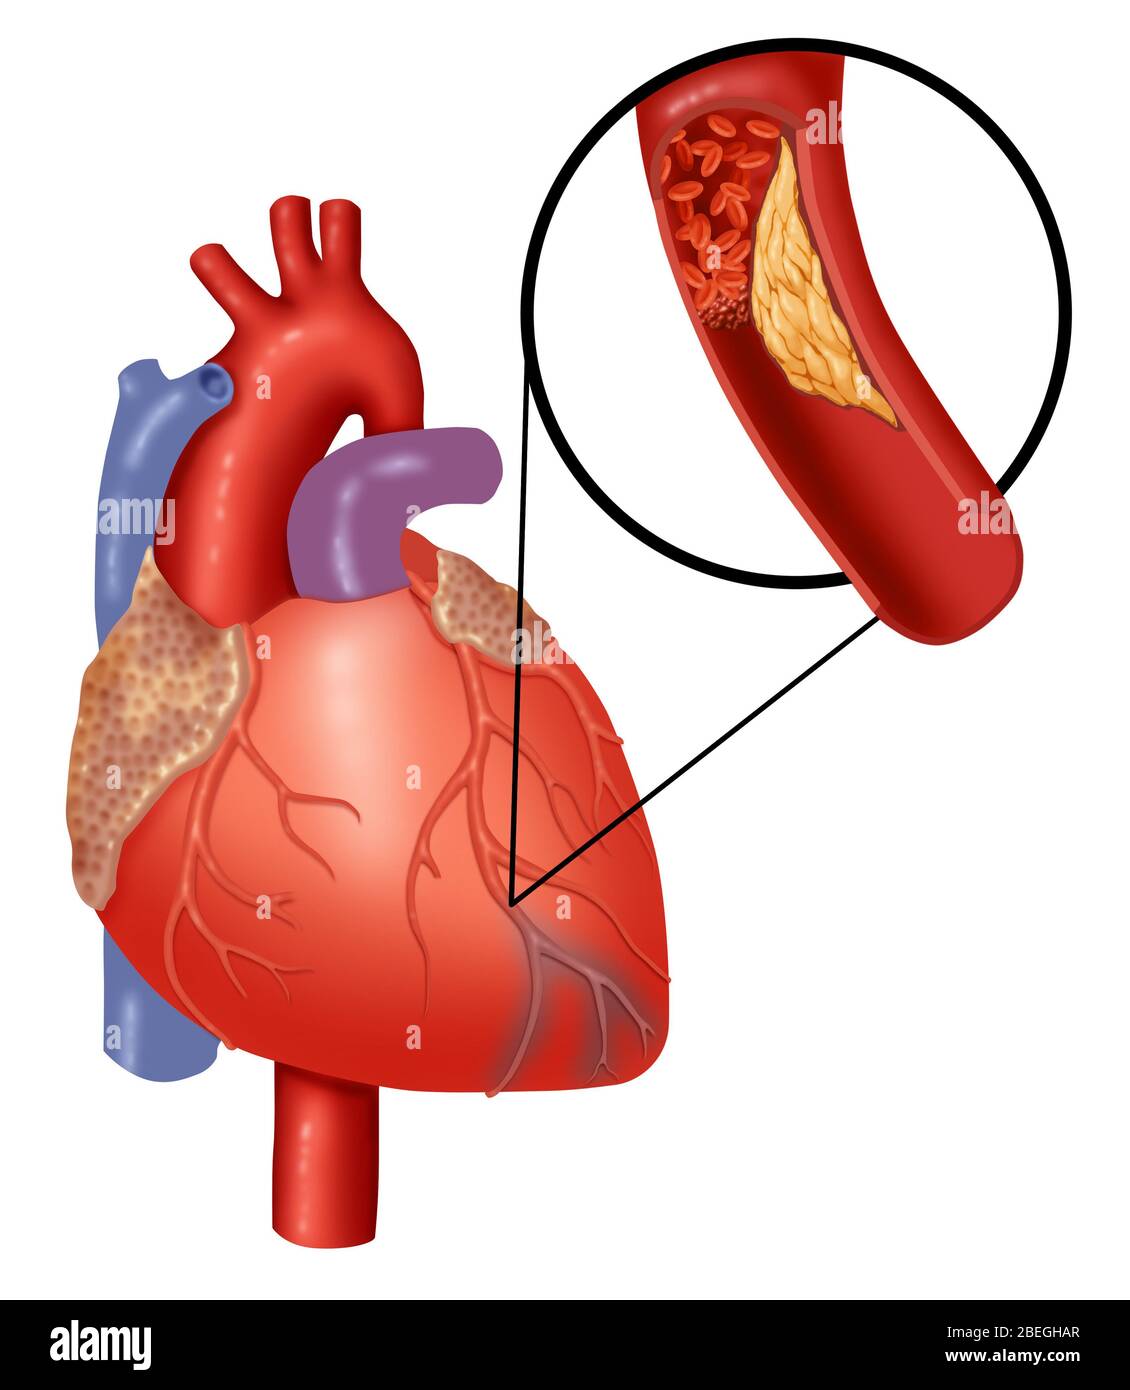

RF2T6GG1J–Photomikrographie des Myokardinfarkts, Darstellung von beschädigtem Herzgewebe durch verminderte Blutversorgung und Zelltod.